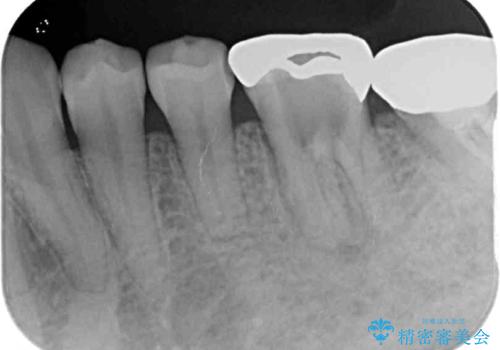

- 高校生の時に行った矯正治療の後戻りと、通院してもなかなか改善しない奥歯の痛みを気にして来院された患者様です。

左下奥歯は、前医より難治性なので抜歯も考えるよう言われたそうですが、一度もラバーダムを用いた根管治療はされていないとのことでした。

まずは左下奥歯の根管治療を行い、痛みが引いたことを確認してから矯正治療を開始しました。